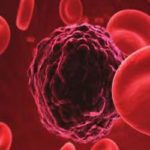

Ultrasonography Services

Laboratory/Pathology Services